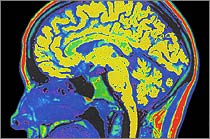

I work in a research lab at McLean Hospital, which is

a psychiatric teaching hospital and research center affiliated with Harvard Medical School.

As part of the Brain

Imaging Center, our lab takes pictures of the chemical changes inside

the brain (using MRS, Magnetic Resonance Spectroscopy). Our particular interest is in mental illness and addiction in adolescents. |